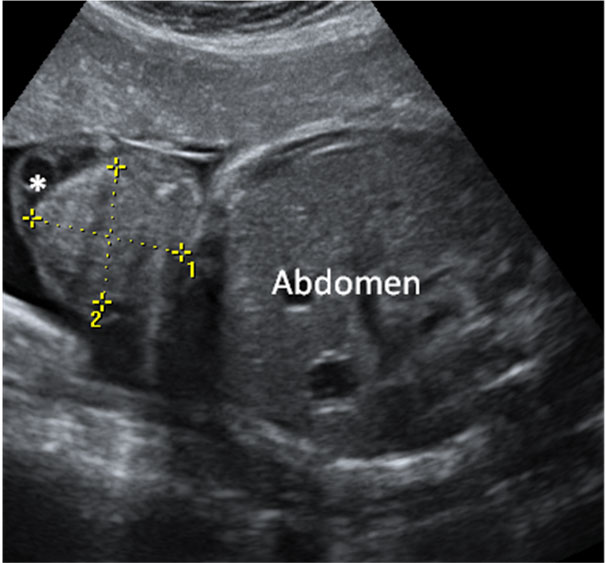

Ecografía Embarazo 2D y 3D Semana 20 - MALFORMACIONES FETALES